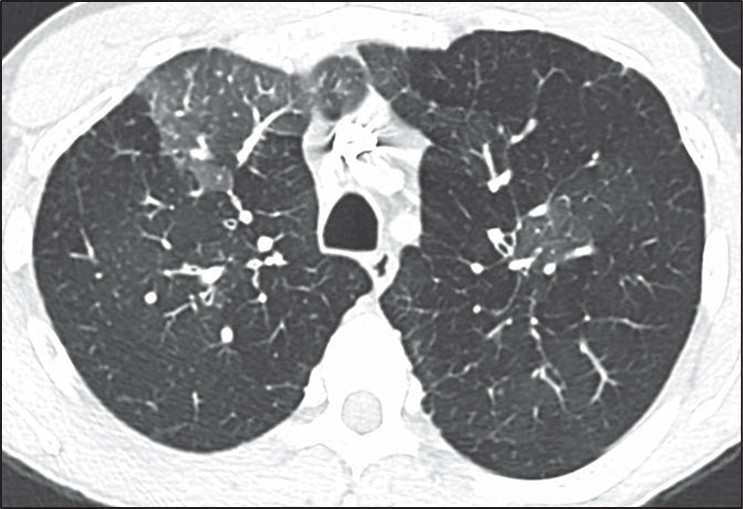

Many of the pitfalls in correctly identifying honeycombing and distinguishing honeycombing from mimics can also be applied to the correct diagnosis of cystic lung disease. When considering a potential diagnosis of cystic lung disease, it is important to again identify mimics: honeycombing, dilated airways and bronchiectasis, and emphysema. The extent of abnormality, from mild to severe, is also important to consider in this context. A few scattered pulmonary cysts may be considered in the spectrum of normal, particularly for older patients, and are most likely postinfectious rather than indicative of a cystic lung disease [14].Whereas the primary features of bronchiectasis (i.e., tubular shape) and honey- combing (i.e., thick walls, clustered, subpleural) make distinguishing these entities from cystic lung disease more straightforward, correctly distinguishing cystic lung disease from emphysema can be challenging. This challenge is in part because both entities can have very thin or imperceptible walls and can occur on a spectrum from mild to severe. The presence of the “central dot” sign in which the centrilobular artery is seen within an emphysematous space can be helpful in correctly distinguishing centrilobular emphysema from a cystic lung disease; however, this finding is not reliably seen in all regions of emphysema [15] (Fig. 6).

Fig. 6—Axial HRCT scan shows “central dot” sign in patient with centrilobular emphysema.